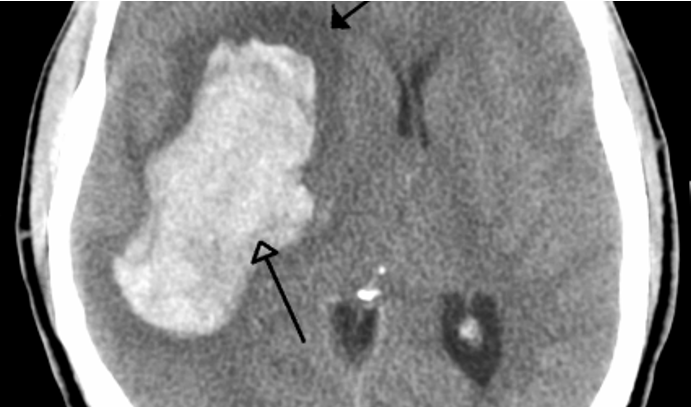

What stroke has the following appearance on a head CT?

bright/white & seen earlier

hemorrhagic stroke

What is the MC underlying cause of non-traumatic intracerebral hemorrhages?

HTN

What are potential bleeding sites of intracerebral hemorrhages?

deep cerebral (putamen, thalamus), lobar (subcortical), pons, cerebellar